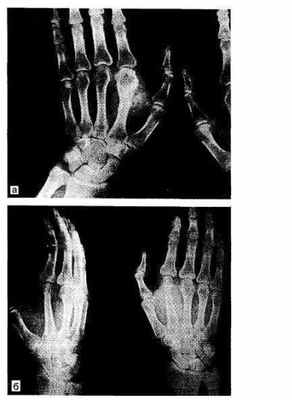

Рис.24.1. Хондросаркома II пястной кости левой кисти (а). Удаленная II пястная кость замещена IV плюсневой костью (б).

У ряда больных были показания к транслюмбальной ампутации (ниже II поясничного позвонка). С родственниками 3 больных мы беседовали, но они категорически отказались от этой операции, как и сами больные, которые еще хорошо ходили; 6 больным была произведена межлопаточно-грудная ампутация, а 38 — межлопаточно-грудная резекция — эту операцию необходимо широко пропагандировать. 25 больным выполнены ампутации конечностей на различном уровне и 12 — ампутации пальцев. Остальным пациентам были произведены различные другие сохранные операции (рис. 24.1, 24.2).